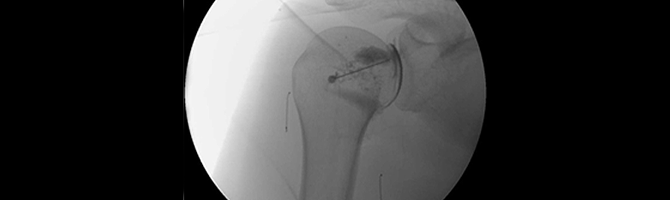

• 관절강 내 유착박리술